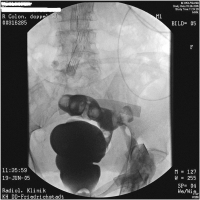

Fistelnachweis

Abbildung 4: Kontrastmitteleinlauf mit Fistelnachweis zur linken Leiste